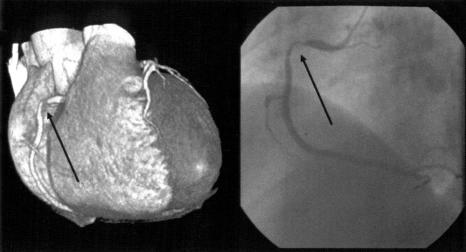

Contrast-enhanced multi-detector row spiral computed tomography (MDCT) was introduced as a promising noninvasive method for vascular imaging. This study examined the accuracy of this technique for detecting significant coronary artery stenoses. Both MDCT(Sensation 16, Siemens, Germany, 12x0.75 mm collimation and 0.42 sec rotation speed, 120 kV, 500 effective mA, and 2.7 mm/rotation table-feed) and invasive coronary angiography (CAG) were performed on 61 patients (mean age 59.2+/-10, 44 men) who were suspected of having coronary artery disease. All patients were treated with atenolol (25-50 mg) prior to imaging and the heart rate was maintained below 65 beats per minutes during image acquisition. The images were reconstructed in the diastole around TI-400 ms with a 0.5 mm increment and a 1.0 mm thickness. All coronary arteries with a diameter of 2.0 mm or more were assessed for the presence of a stenosis (>50% luminal narrowing). Two independent radiologists who were unaware of the results of the invasive CAG evaluated the MDCT data, and the results were compared with those from the invasive CAG (interval 1-27, mean 11 days). An evaluation of the CT coronary angiogram (CTCA) was possible in 58 of the 61 patients (95%). Image acquisition of the major coronary arteries including the left main trunk was available in 229 out of 244 arteries. Invasive CAG showed that 35 out of 58 patients had significant coronary artery stenoses by. patient analysis of those who could be evaluated showed that CT coronary angiography correctly classified 30 out of 35 patients as having at least 1 coronary stenosis (sensitivity 85.7%, specificity 91.3%, positive predictive value 93.8%, negative predictive value 80.8%). By analyzing each coronary artery, CAG found 62 stenotic coronary arteries in the 229 coronary arteries that could be evaluated. MDCT correctly detected 50 out of 62 stenotic coronary arteries and an absence of stenosis was correctly identified in 156 out of 167 normal coronary arteries (sensitivity 80.6%, specificity 93.4%, positive predictive value 81.9%, negative predictive value 92.8%). The non-invasive technique of MDCT for examining the coronary artery appears to be a useful method for detecting coronary artery stenoses with a high accuracy particularly with the proximal portion and large arteries.

对比增强型多排螺旋计算机断层扫描(MDCT)作为一种有前景的血管成像无创方法被引入。本研究检测了该技术检测显著冠状动脉狭窄的准确性。对61例疑似患有冠状动脉疾病的患者(平均年龄59.2±10岁,44例男性)同时进行了MDCT(德国西门子Sensation 16,准直12×0.75mm,转速0.42秒,120kV,有效毫安500,床进速度2.7mm/旋转)和有创冠状动脉造影(CAG)检查。所有患者在成像前均接受阿替洛尔(25 - 50mg)治疗,且在图像采集期间心率维持在每分钟65次以下。图像在舒张期TI - 400ms左右重建,增量为0.5mm,层厚为1.0mm。对所有直径2.0mm及以上的冠状动脉评估是否存在狭窄(管腔狭窄>50%)。两名不知有创CAG结果的独立放射科医生评估MDCT数据,并将结果与有创CAG的结果进行比较(间隔1 - 27天,平均11天)。61例患者中有58例(95%)可行CT冠状动脉造影(CTCA)评估。244支动脉中有229支获得了包括左主干在内的主要冠状动脉的图像采集。有创CAG显示,58例患者中有35例存在显著冠状动脉狭窄。对可评估患者的分析显示,CT冠状动脉造影将35例患者中的30例正确分类为至少有1处冠状动脉狭窄(敏感性85.7%,特异性91.3%,阳性预测值93.8%,阴性预测值80.8%)。通过分析每支冠状动脉,CAG在229支可评估的冠状动脉中发现62支狭窄冠状动脉。MDCT正确检测出62支狭窄冠状动脉中的50支,在167支正常冠状动脉中的156支正确识别出无狭窄(敏感性80.6%,特异性93.4%,阳性预测值81.9%,阴性预测值92.8%)。MDCT这种用于检查冠状动脉的无创技术似乎是一种检测冠状动脉狭窄的有用方法,尤其对于近端部分和大动脉具有较高的准确性。